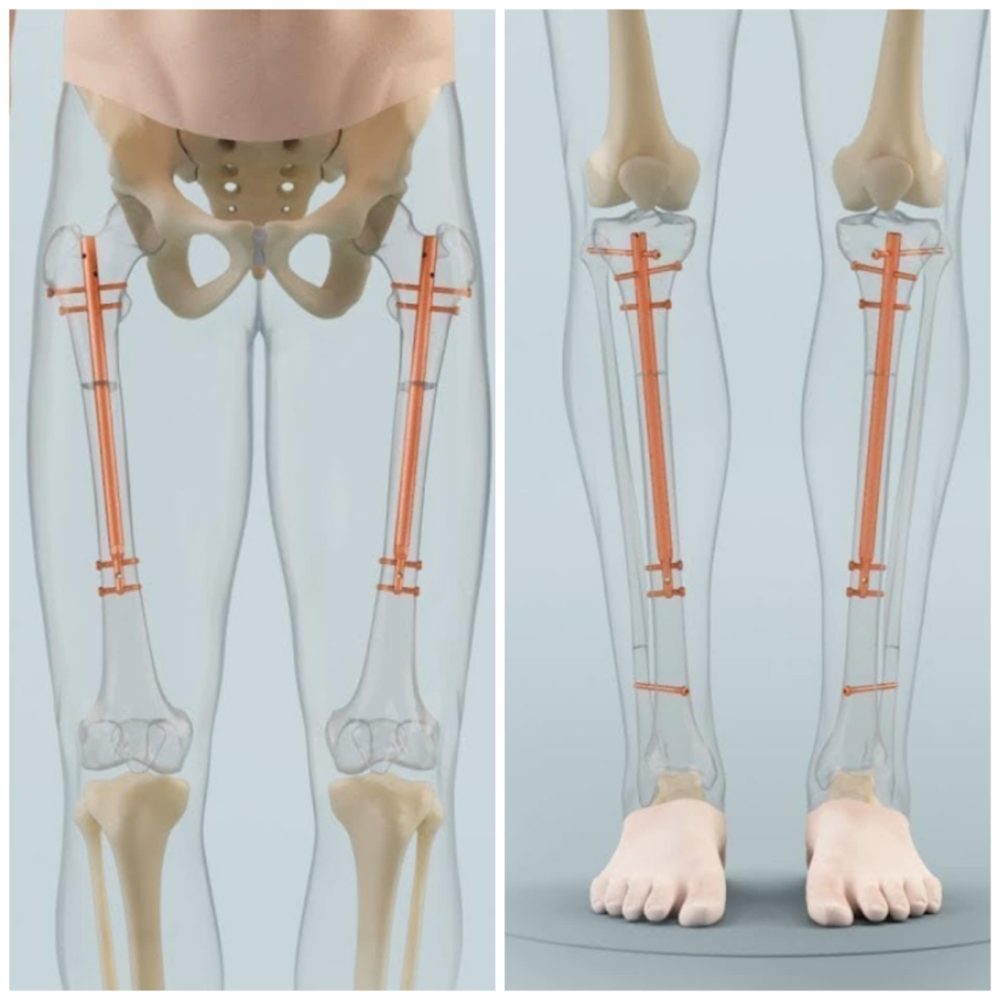

Nekada su se koristile spoljašnje fiksacije poput Ilizarov aparata, koje su bile bolne, spore i zahtevale mesece nošenja metalnih prstenova. Danas su dostupni moderni intramedularni sistemi – teleskopske šipke koje se ugrađuju unutar kosti i koje omogućavaju precizno, postepeno i komforno produženje. Nove tehnologije skraćuju vreme rehabilitacije, smanjuju rizik od infekcija i omogućavaju ranije vraćanje svakodnevnim aktivnostima, uz znatno bolje estetske rezultate.

Intramedullary Limb Lengthening ili Internal Nail Limb Lengthening Moderna metoda koja koristi teleskopsku šipku ugrađenu u kost (npr. Precice, Fitbone, druge varijante).

Intramedularno produženje se najčešće radi na butnoj kosti (femur), jer ona ima veliku medularnu šupljinu i dobro zarasta. Po potrebi, produženje je moguće uraditi i na potkolenici (tibia), što je češće kada pacijent želi dodatnih nekoliko centimetara ili kada proporcije nogu to zahtevaju. Produženje na tibiji može biti sporije i zahtevnije za rehabilitaciju, pa se ponekad kombinuje sa femoralnim produženjem u dve faze.